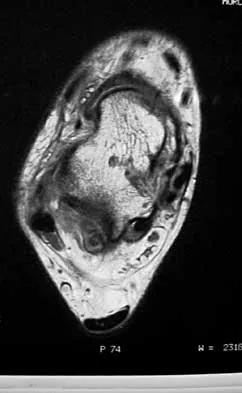

A 35-year-old woman dislocated her right shoulder in a fall from a step stool several months ago. She now reports several painful recurrences. Examination reveals anterior and inferior apprehension that reproduces her symptoms. An MRI scan is shown in Figure 17. Management should consist of

Explanation